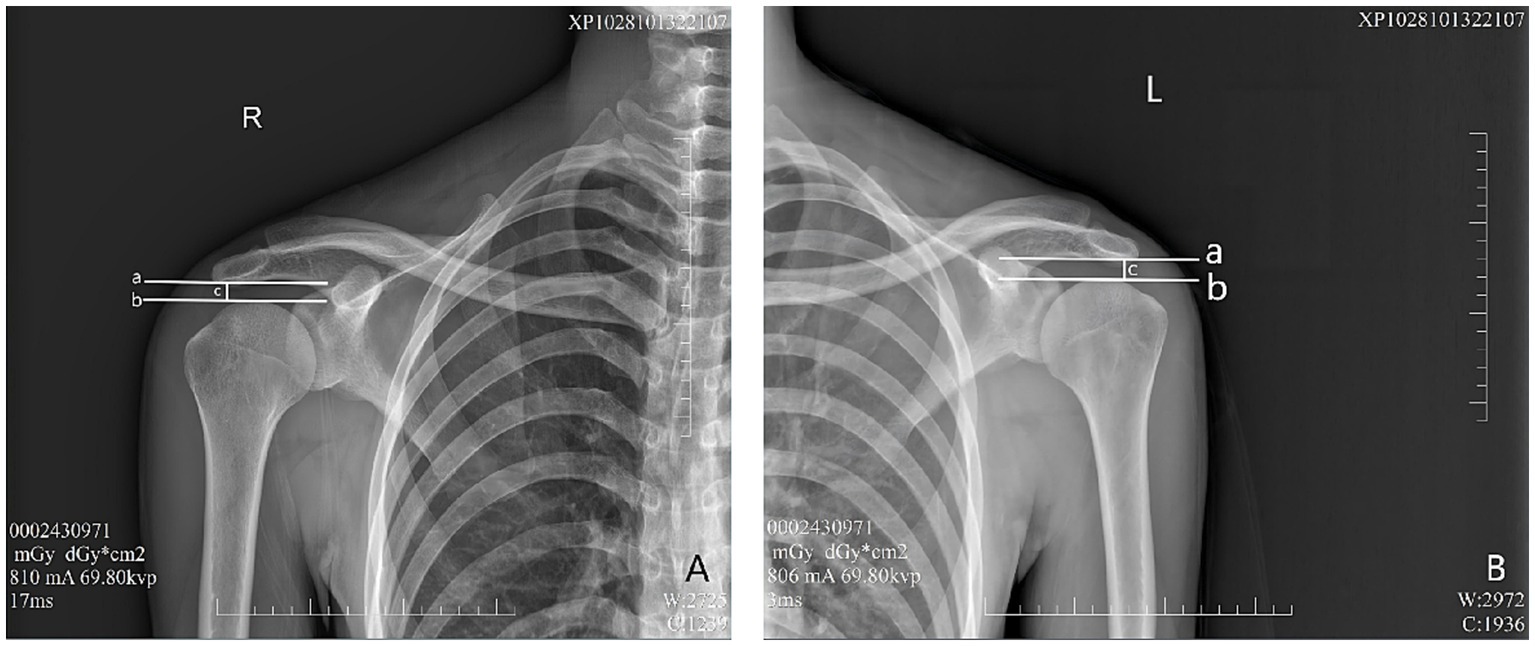

Figure 2

Evaluation of AHD distance from the healthy participant to the flat plane detector at 0 cm. a—A horizontal vertical line across the lowest point of the acromion. b—A horizontal line across the top of the humeral head. c—Distance between lines A and B, as well as AHD. (A) Right shoulder, (B) Left shoulder.

Figure 3

Evaluation of AHD distance from the healthy participant to the flat plane detector at 50 cm. a—A horizontal vertical line across the lowest point of the acromion. b—A horizontal line across the top of the humeral head. c—Distance between lines A and B, as well as AHD. (A) Right shoulder, (B) Left shoulder.

In the evaluation of AHD during radiographic procedures, the research included 28 healthy participants based on the informed consent of each participant. During the assessment via radiography (Simens Yiso, Fluorospot compact imaging systems, Germany) (Parameter settings: tube voltage 70 kV, automatic tube current, and small focal spot), participants were asked to maintain an upright position with their arms resting comfortably alongside their bodies and palms oriented towards their torso (Figures 1A,B). A vertical reference line was marked from the lowest point of the acromion, perpendicular to a horizontal line drawn from the top of the humeral head, which allowed for the measurement of the distance between the acromion and the humeral head (17) (Winning Health TView 6.1.0, Winning Health Technology Group Co., Ltd.) (Figures 2, 3). And the ratio of the bilateral distances was calculated (Left/Right). These procedures were performed by a single radiologist. It was made that the consistency of the results was evaluated for the distances from the healthy participant to the flat plane detector, measuring at 0 cm and 50 cm (Figures 1–3).